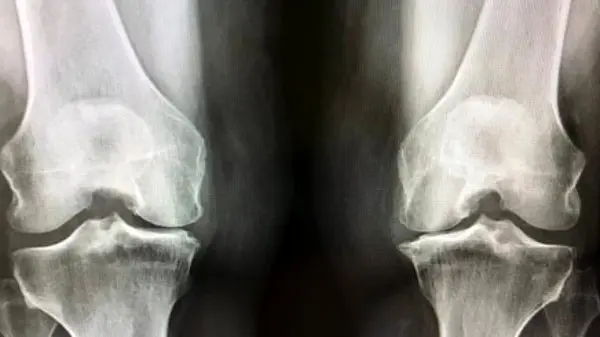

به گزارش رکنا، دکتر منصور مرادی، متخصص ارتوپدی در کردستان، اعلام کرد که آرتروز زانو به عنوان تحلیل رفتن غضروف میان دو استخوان شناخته میشود. این موضوع با افزایش سن، وزن بیش از حد، و روش زندگی نادرست ممکن است شکل بگیرد. یکی از عمدهترین دلایل این بیماری، پیشرفت سن است که با آن، تحلیل رفتن غضروف شدت میگیرد. همچنین، افزایش وزن و سبک زندگی ناصحیح نیز خطر ابتلا به آرتروز را میافزاید.

دکتر مرادی تاکید کرد که در صورت بروز زانو درد، مراجعه به پزشک و انتخاب تصمیمات درمانی مناسب، از اهمیت زیادی برخوردار است. متأسفانه، هیچ داروی کاملاً مؤثری برای درمان آرتروز موجود نیست و این وضعیت ممکن است به جراحی تعویض مفصل منجر شود.